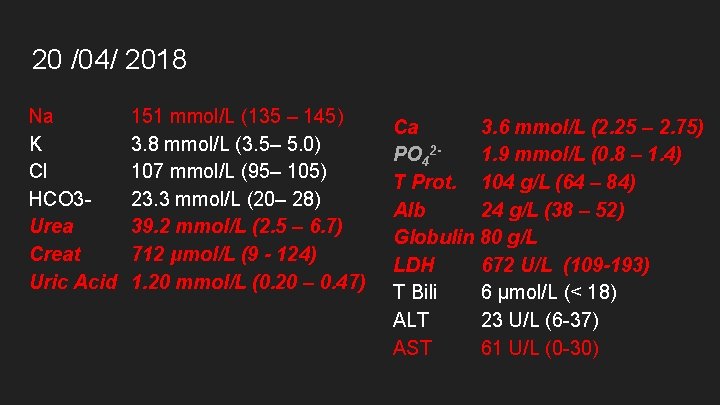

20 /04/ 2018 Na K Cl HCO 3 Urea Creat Uric Acid 151 mmol/L (135 – 145) 3. 8 mmol/L (3. 5– 5. 0) 107 mmol/L (95– 105) 23. 3 mmol/L (20– 28) 39. 2 mmol/L (2. 5 – 6. 7) 712 μmol/L (9 - 124) 1. 20 mmol/L (0. 20 – 0. 47) Ca 3. 6 mmol/L (2. 25 – 2. 75) PO 421. 9 mmol/L (0. 8 – 1. 4) T Prot. 104 g/L (64 – 84) Alb 24 g/L (38 – 52) Globulin 80 g/L LDH 672 U/L (109 -193) T Bili 6 μmol/L (< 18) ALT 23 U/L (6 -37) AST 61 U/L (0 -30)

20 /04/ 2018 - Results Na K Cl HCO 3 Urea Creat Uric Acid 151 mmol/L (135 – 145) 3. 8 mmol/L (3. 5– 5. 0) 107 mmol/L (95– 105) 23. 3 mmol/L (20– 28) 39. 2 mmol/L (2. 5 – 6. 7) 712 μmol/L (9 - 124) 1. 20 mmol/L (0. 20 – 0. 47) Ca 3. 6 mmol/L (2. 25 – 2. 75) PO 421. 9 mmol/L (0. 8 – 1. 4) T Prot. 104 g/L (64 – 84) Alb 24 g/L (38 – 52) Globulin 80 g/L LDH 672 U/L (109 -193) T Bili 6 μmol/L (< 18) ALT 23 U/L (6 -37) AST 61 U/L (0 -30)